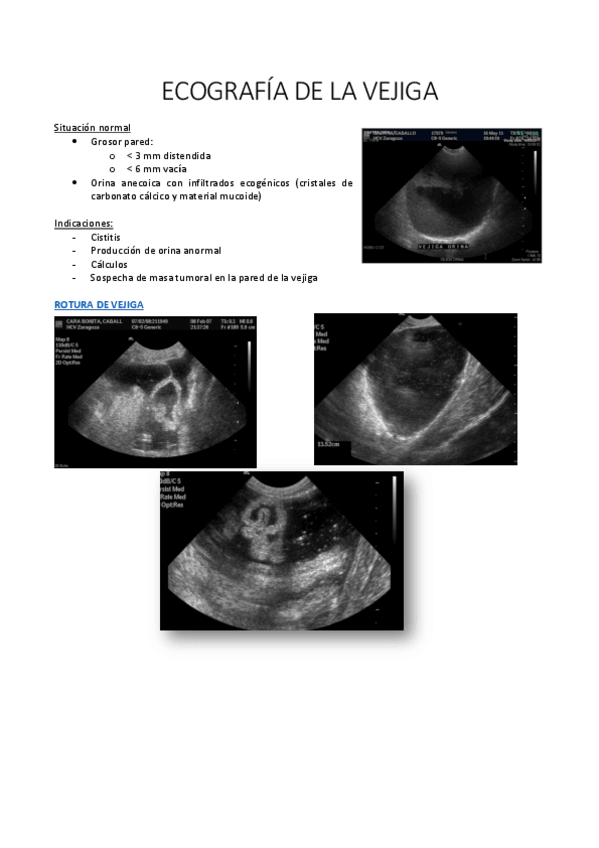

ÉQUIDOS dx imagen

He publicado nuevos apuntes de 3º Diagnóstico Por Imagen: ÉQUIDOS dx imagen

ECOGRAFIA-DE-LA-VEJIGA.pdf